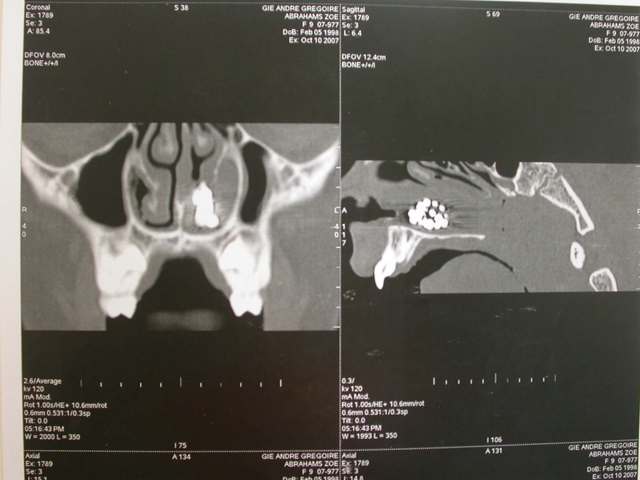

Je décide donc de faire réaliser un scanner et là c’est nouveau pour vous.

Une fois le scanner réalisé, je vois bien qu’il s’agit d’un objet composé de boules et l’adresse illico à son orl. Il la reçoit dans la foulée, et au vu du scanner, se refuse d’intervenir de peur de renvoyer plus loin l’objet. A son tour, il l’adresse à un hopital spécialisé enfants (Robert Debré). Au service ORL, ils tentent de retirer l’objet avec une pince (comme Dr House le faisait dans un épisode) et rien de neuf, aucune progression.